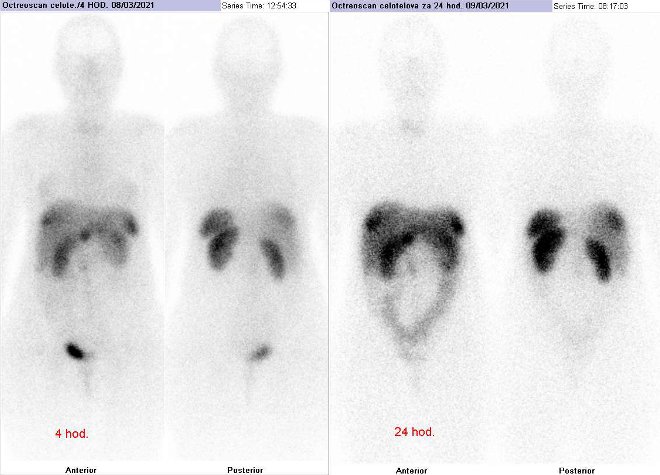

Pomocí dvoudetektorové hybridní tomografické kamery Symbia T2 (SPECT/CT) firmy Siemens opatřené kolimátory pro střední energie jsme provedli celotělovou scintigrafii a také cílenou tomografickou scintigrafii (SPECT) a CT a fúzi obrazů SPECT/CT krku, hrudníku, břicha a pánve za 4 hod. a 24 hod.

(obr. 1-9) po i.v. podání 190 MBq analogu somatostatinu značeného

111In (přípravek OctreoScan firmy Mallinckrodt Medical).

/ Obr. č. 1: Celotělová scintigrafie v přední a zadní projekci. Vyšetření 4 hod. (vlevo) a 24 hod. (vpravo) po aplikaci radioindikátoru.